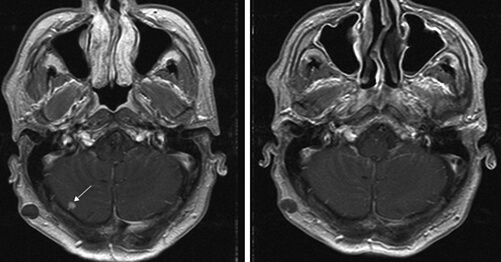

우리 몸에 산소를 공급하는 과정에서 수많은 세균들과 이물질들이 폐에 침범합니다. 그래서 이러한 세균들을 막기 위해서 폐에는 광범위하게 전체적으로 림프절이 분포되어 있습니다. 위에 사진을 보시면 됩니다. 그래서 N은 이렇게 폐에 분포되어 있는 림프절로 폐암이 얼마나 전이 됐는가를 구분하는 것입니다.